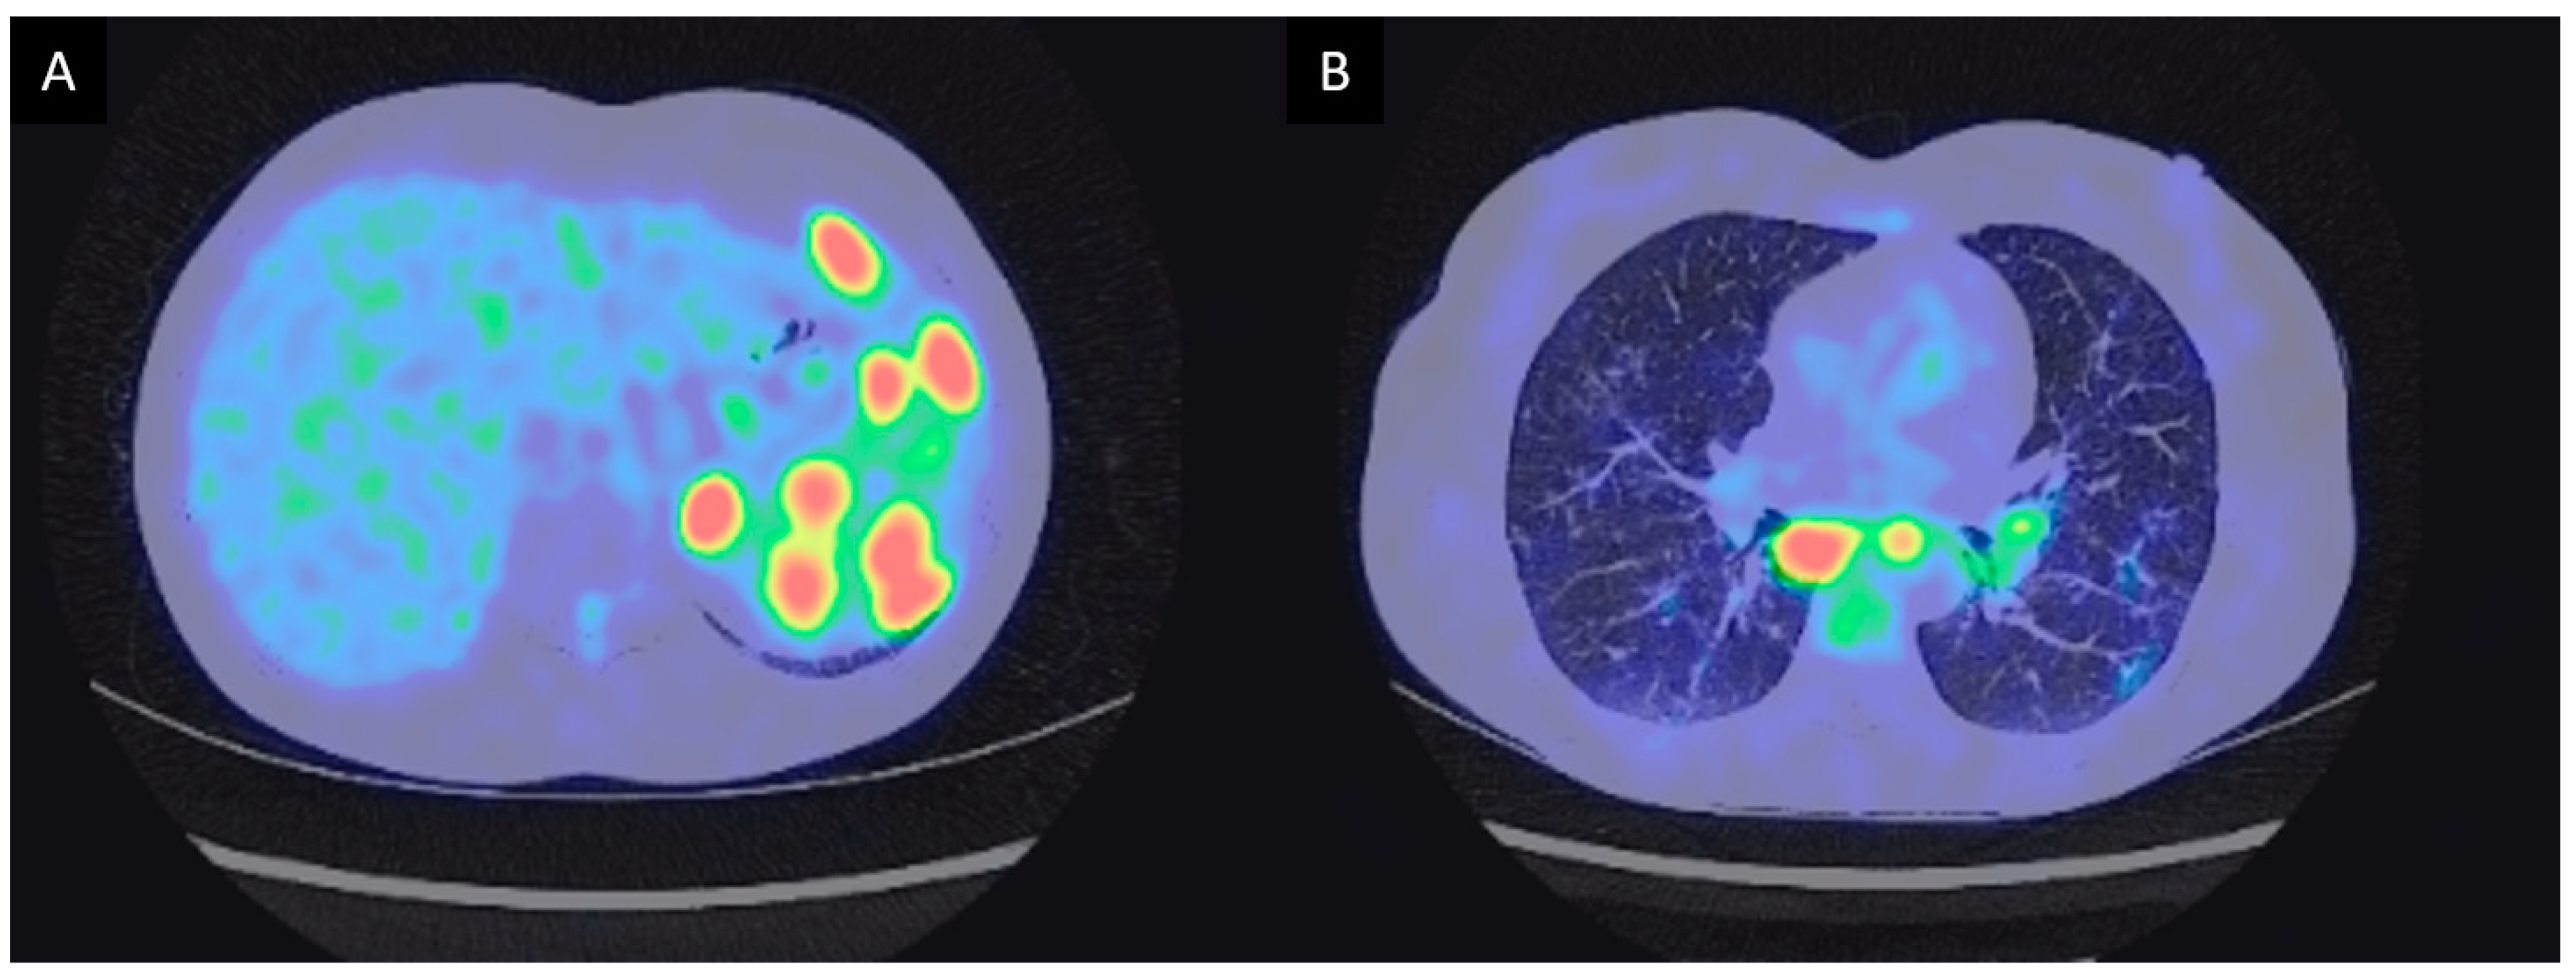

3.2. Neoplastic Disorders

3.2.1. Case Description

| 3 | M | 45 | Maghrebian | Altered general condition with 2 kg weight loss. Hard, fixed and painless left sus clavicular and cervical adenopathies. Sino nasal obstruction with retropharyngeal adenopathies with cavum mucosal thickening | Atypical lymphadenopathies, exclusive extrathoracic multi organ involvement. | 24 months | Hodgkin’s lymphoma | Chemotherapy (ABVD, ICE) | Currently continuing chemotherapy |

| 4 | F | 56 | Caucasian | Cervical and axilar lymph nodes. Cavum tumefaction. Granulomas without atypical features. Atypical CD30+ cells on repeated lymph nodes sampling. | Cavum infiltration and exclusive extrathoracic lymph nodes. | 72 months | Biclonal lymphoma (Hodgkin and Diffuse large B cell lymphoma). Hodgkin disease was already present at disease onset 6 years before (second-look histological examination). | Chemotherapy (R-CHOP 8x) | Healing |

| 5 | M | 54 | Maghrebian | Lower esophagus stenosis with peri esophageal adenopathies and dysphagia. Paratracheal and subcarinal and antero superior mediastinal lymph nodes. Histological examination concordant with Piringer Kuchinka’s lymphadenitis. | Compressive phenomenon. No hilar lymph nodes with anterior mediastinal lymph nodes. | 40 months | EBV positive Hodgkin’s lymphoma | ABVD 6 courses | Healing |

| 7* | F | 63 | Caucasian | Bilateral anterior and intermediate uveitis. Granuloma on MSGB. Gait disturbance with multiple supra tentorial demyelinating lesions on FLAIR-weighted sequences. | Corticoresistant uveitis and neurological involvement. | 3 years | Vitroretinal lymphoma. | R-Metho AraC chemotherapy followed by ibrutinib and R-VP16-Holoxan. | The patient died 3 months after the diagnosis [204]. |